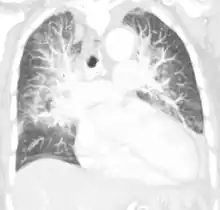

| Pulmonary edema with small pleural effusions on both sides | |

Low oxygen saturation in blood and disturbed arterial blood gas readings support the proposed diagnosis by suggesting a pulmonary shunt. A chest X-ray will show fluid in the alveolar walls, Kerley B lines, increased vascular shadowing in a classical batwing peri-hilum pattern, upper lobe diversion (biased blood flow to the superior parts instead of inferior parts of the lung), and possibly pleural effusions. In contrast, patchy alveolar infiltrates are more typically associated with noncardiogenic edema[2]